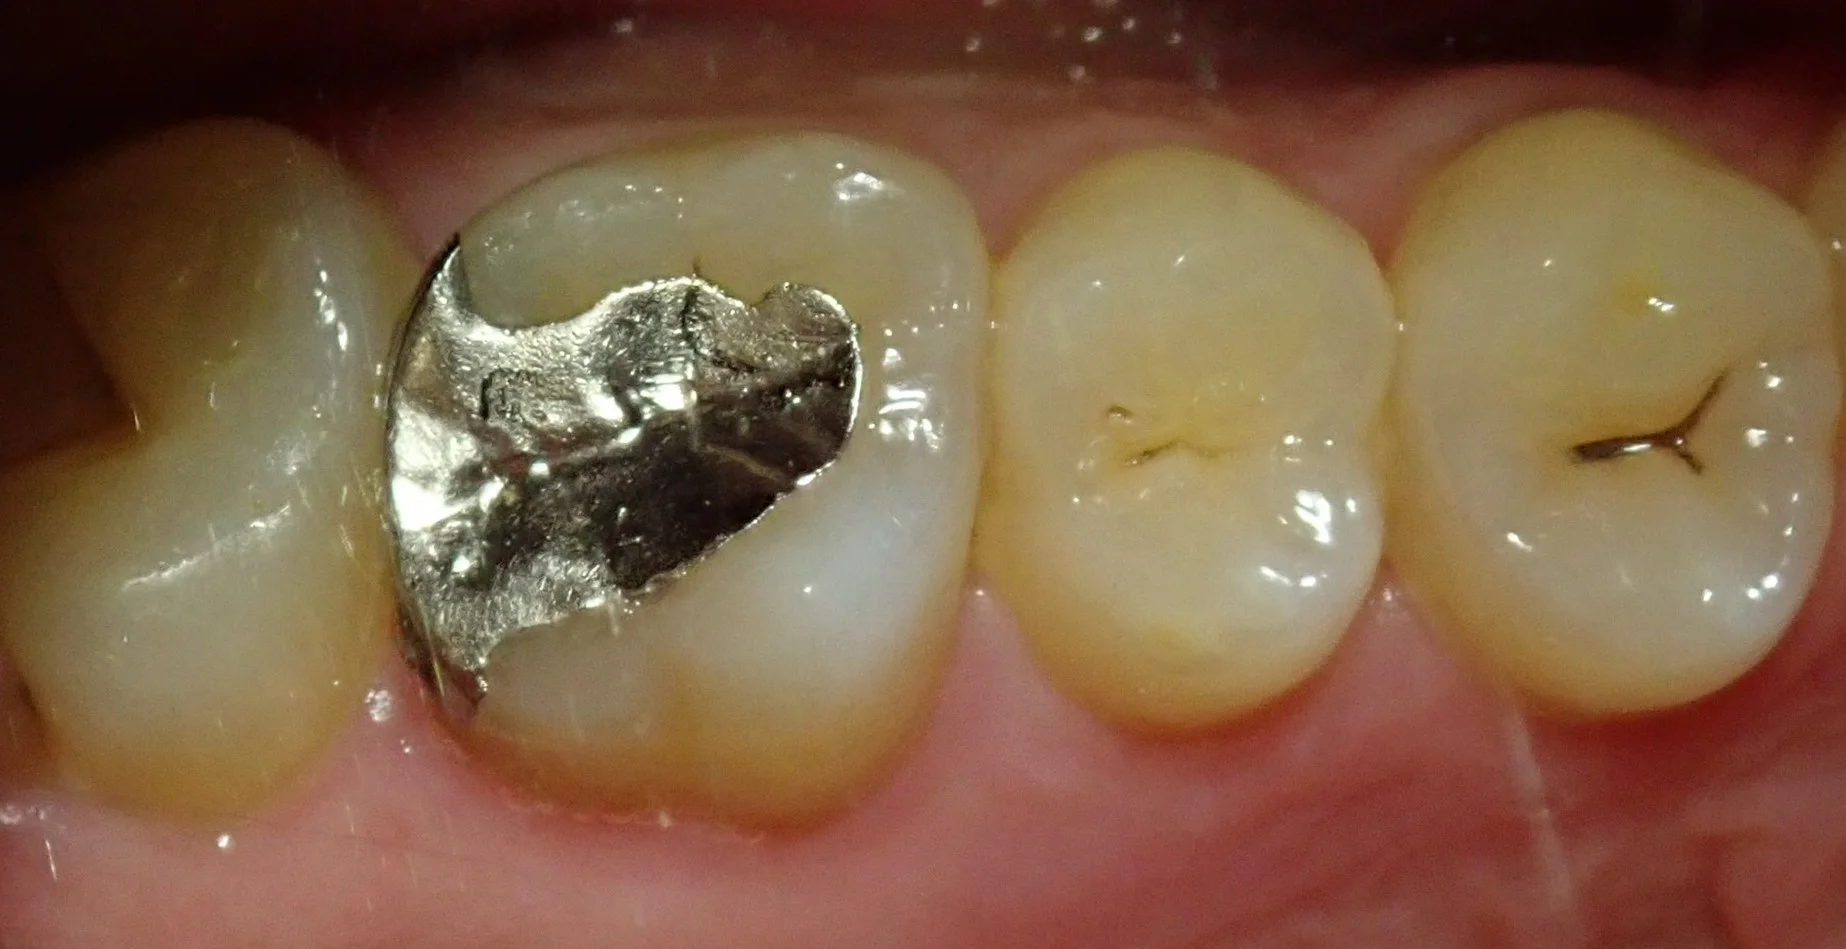

まずはいつも通り、術前写真から。

この金属部分が虫歯になってしまっているので、ここを治療していきました。

元々入っている金属自体の適合は決して悪くはありません。

ですが、金属の詰め物被せ物は歯に直接くっつけることが出来ませんので、セメントを介して歯にくっつけることになります。

ですが、そのセメントも長い年月をかけてボロボロと取れていき・・・

そこの隙間から虫歯になってしまうという事が多々あります。